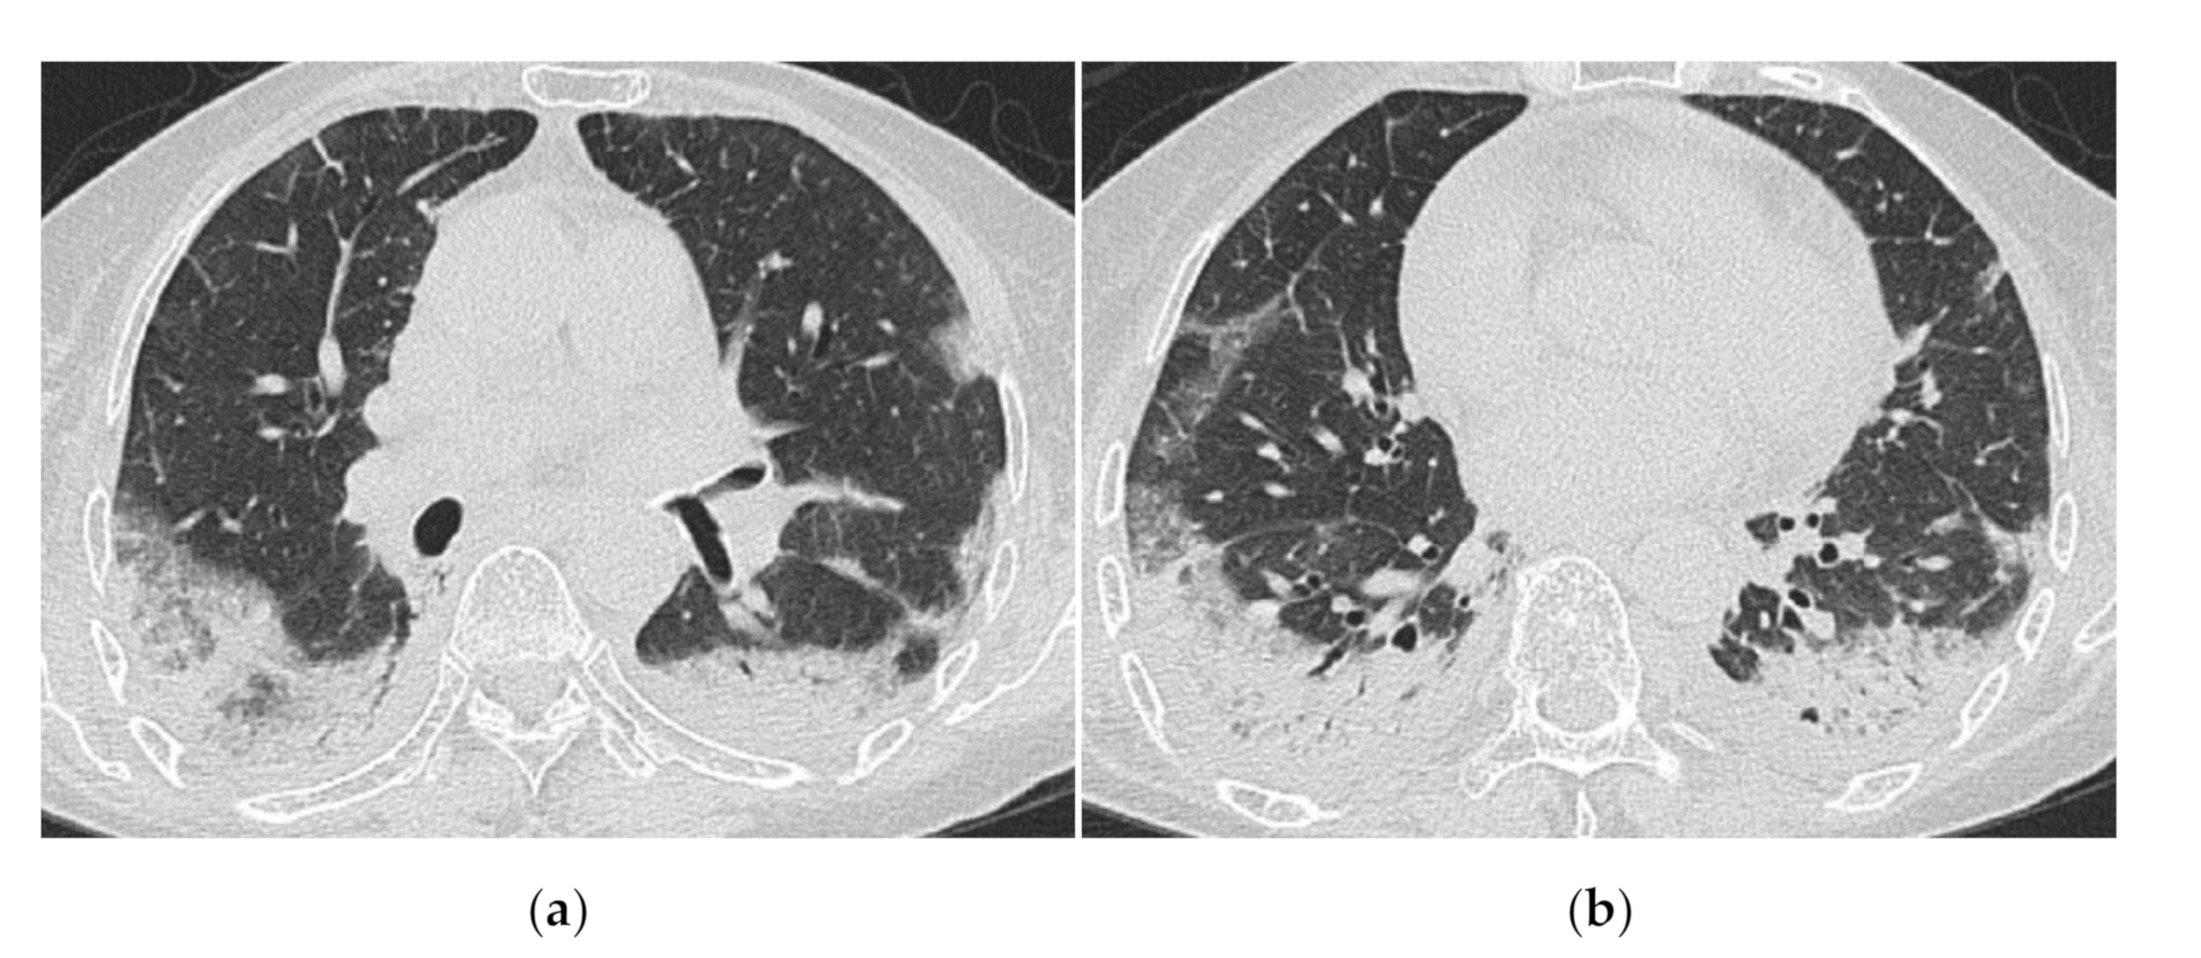

3.1. Anti-Aminoacyl tRNA Synthetase Antibody (Anti-ARS Ab)

HRCT Findings of Patients with Anti-ARS Ab

3.2. Anti-MDA5 Antibody (Anti-MDA5 Ab)

HRCT Findings of Patients with Anti-MDA5 Ab